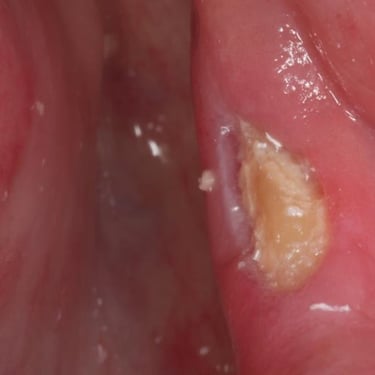

Infección postoperatoria

La infección postoperatoria puede ocurrir después de una cirugía maxilofacial, manifestándose con dolor, hinchazón, fiebre y supuración.

Los pacientes deben estar atentos a estos signos después de la cirugía.

El tratamiento incluye antibióticos y, en algunos casos, la limpieza quirúrgica del área afectada.